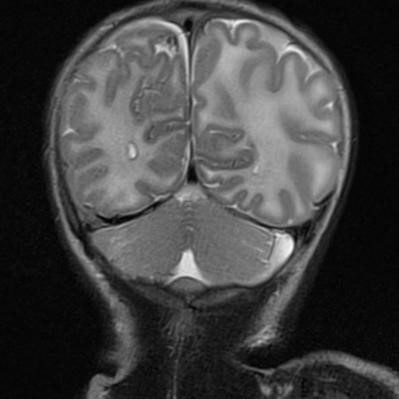

Lactante de 39 días de vida que acude a urgencias por episodio breve resuelto inexplicado, los padres refieren hipotonía e hiporreactividad durante unos minutos en domicilio, recuperándose tras estimulación. Como antecedentes procede de una gestación gemelar, parto a las 34 semanas mediante cesárea por bradicardia fetal sin precisar reanimación. Durante el ingreso en planta presenta dos crisis clónicas de hemicuerpo izquierdo que ceden tras administración de fenobarbital, tras lo cual se inicia monitorización con electroencefalograma de amplitud integrada objetivando nuevos episodios. Se realiza resonancia magnética cerebral, donde se evidencian múltiples focos de sangrado intracraneal y áreas de daño hipóxico-isquémico que sugieren posible trauma no accidental (Figura 1). Posteriormente, se realiza fondo de ojo con hemorragias retinianas y serie ósea con fracturas en diferentes estadios (Figura 2). Dada la situación clínica y la alta sospecha de maltrato infantil se contacta con el juzgado de guardia para valoración del menor. Tras un primer estudio se recomienda ingreso por motivo social de los dos hermanos del paciente, encontrando hallazgos sugestivos de maltrato en una de ellas. Teniendo en cuenta lo anterior, se declara a los menores en situación de desamparo, asumiéndose la tutela de los mismos por parte del Servicio de Menores.

Figura 1. Colección extraxial hemitentorial derecha de 4 mm de espesor compatible con hematoma subdural